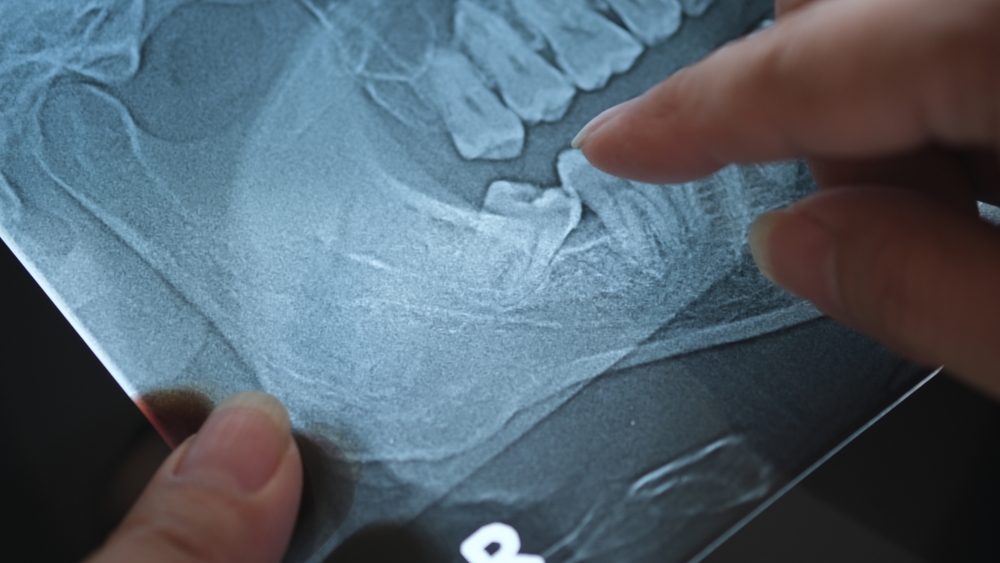

What is an Impacted Tooth? How is Impacted Tooth Treatment Done?

What is an Impacted Tooth? How is Impacted Tooth Treatment Done? 24 July 2025 Blog What is an Impacted Tooth? How is Impacted Tooth Treatment Done? Impacted teeth are teeth that cannot find their natural way out due to a narrow jaw structure or an imbalance in the position of the teeth, and therefore remain […]